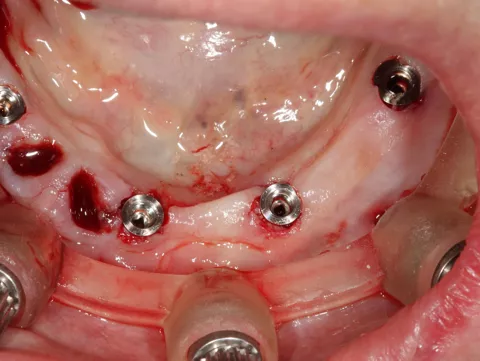

8. Implants are in situ; the procedure was minimally invasive.

9.  Positioning of the Tissue Level temporary abutments platform N plural reference number TC100-N-P to accommodate the prefabricated temporary restoration.